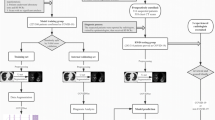

Figure 1 shows the complete pipeline for quantitative COVID-19 assessment. Lesions on chest CT were automatically identified by the intelligent software. Only a few atypical lesions required manual identification (Fig. 2).

Pipeline for quantifying COVID-19 infection A chest CT scan is first fed into the deep learning-based segmentation system. Then, quantitative metrics are calculated to characterize infection regions in the CT scan, including but not limited to the following: infection volumes, and percentages of infection (POIs) in the whole lung, lung lobes, and bronchopulmonary segments